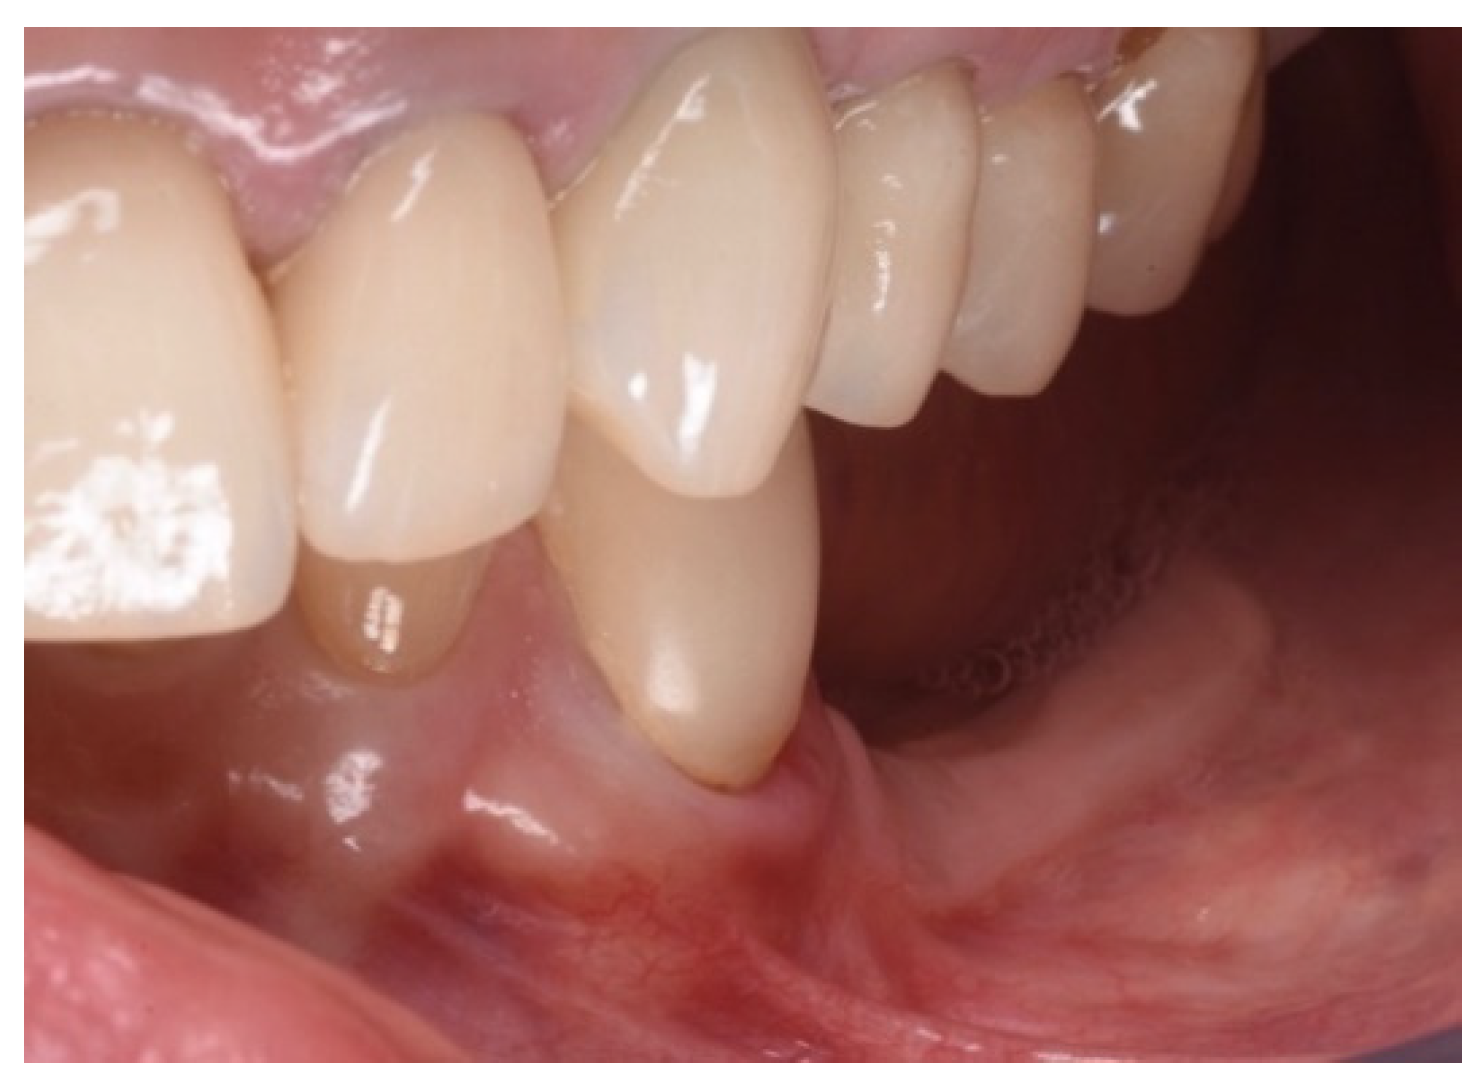

Three months after surgery, the graft showed a healthy color and optimal integration into the surrounding tissues. The mucogingival surgery provided good protection for the subsequent hard tissue regeneration (Figure 5).

Figure 5.

Soft tissue healing at three months.